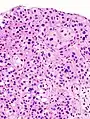

Histopathology of transitional carcinoma of the urinary bladder. Transurethral biopsy. Hematoxylin and eosin stain. | |

Transitional refers to the histological subtype of the cancerous cells as seen under a microscope.

- Histopathology of urothelial carcinoma of the urinary bladder, showing a nested pattern of invasion. Transurethral biopsy. Hematoxylin and eosin.

- Histopathology of urothelial carcinoma of the urinary bladder.

- Micrograph of urethral urothelial cell carcinoma. Hematoxylin and eosin stain.